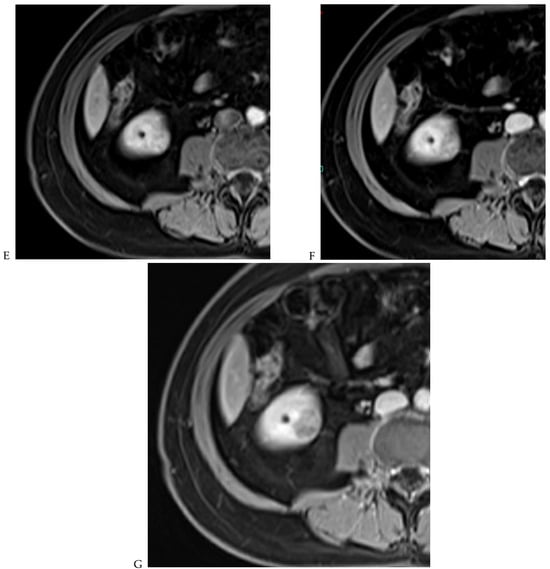

Figure 7.

Papillary renal cell carcinoma in the right kidney of a 75-year-old-woman. (A) Axial T2-weighted fast SE image shows a homogeneous 1.8 cm mass in the posterolateral region of the right kidney, with a lower SI compared to renal parenchyma. Transverse in-phase (B,C) opposed-phase MR images do not show a significant signal loss on the opposed-phase image. (D) The ADC map shows restriction of tumor diffusion into the renal mass. Transverse nonenhanced (E) and gadolinium-enhanced T1-weighted gradient-echo spoiled MR images in (F) corticomedullary, (G) nephrographic, (H) and delayed phase images show progressive enhancement without washout; the mass is hypovascular compared to the renal cortex.

The detection of macroscopic fat in a renal mass is essential because, in the absence of calcification, it is almost always characteristic of a classic (fat-rich) angiomyolipoma, the most common solid benign renal mass. The macroscopic fat component shows a loss of signal intensity on T1-weighted fat-suppressed images. Angiomyolipomas are also characterized by the presence of an India ink artifact on opposed-phase T1-weighted images at the junction of the mass and normal renal parenchyma, indicating a fat–water interface. T1-weighted gradient-echo inversion recovery imaging allows the detection of microscopic/intracytoplasmic fat. Microscopic intracellular fat is present in clear cell RCC (Figure 5), resulting in a signal drop on opposed-phase images. A signal drop has also been described in angiomyolipomas, including fat-poor angiomyolipomas (Figure 6). Gadolinium-enhanced T1-weighted three-dimensional fat-suppressed gradient-echo imaging is useful to assess the enhancement pattern in a renal mass. It allows the differentiation of hypervascular masses from hypovascular lesions with late and slow enhancement as seen in papillary RCC (Figure 7). T2-weighted sequences are essential for differentiating cystic renal masses from solid renal masses. The T2 signal intensity of a solid renal mass is also helpful in suggesting certain histologic subtypes of RCC. Both fat-poor angiomyolipomas (Figure 6) and papillary RCCs (Figure 7) have a low signal intensity on T2-weighted images, whereas other renal masses have an intermediate or high signal intensity. Several studies have suggested the potential utility of apparent diffusion coefficient (ADC) values to further characterize a renal mass [38]. Both fatty angiomyolipomas and papillary RCCs have low ADC values.